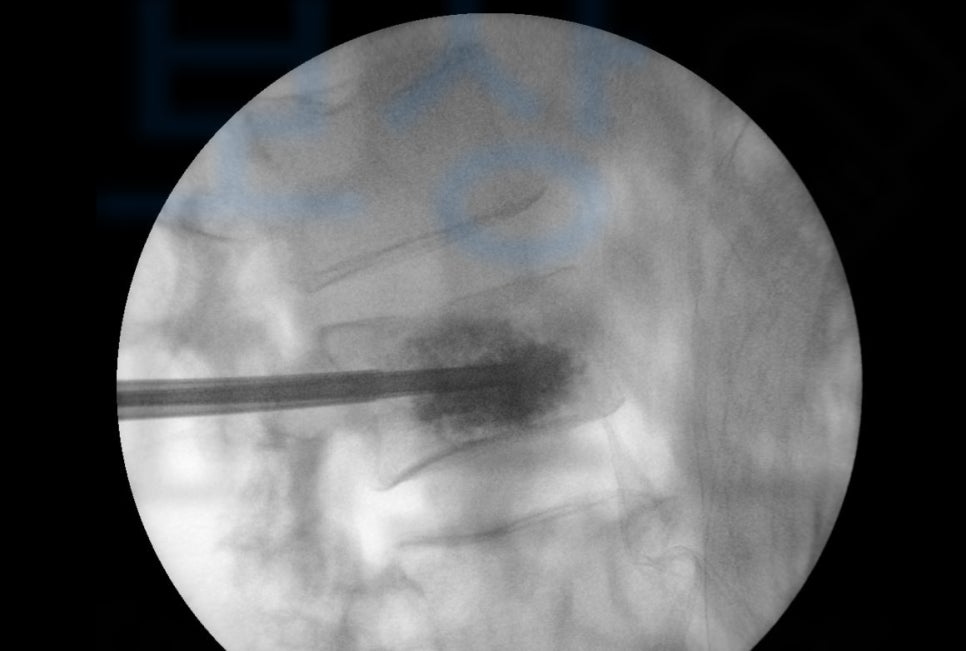

Kyphoplasty 은 경피적 풍선 척추 성형술 로서 골절된 척추체의 압박률이 커서 척추에 심한 변형이 예상되는 경우 골절된 척추체에 확장성 풍선을 삽입 후 척추체의 높이를 충분히 증가 시킨 후 빈 공간에 골시멘트를 채우는 시술입니다.

Vertebroplasty은 경피적 척추 성형술 로서 골절된 척추체에 바로 주사바늘을 넣어 골시멘트를 주입하여 척추뼈를 단단히 굳히는 시술입니다.

압박골절 진단을 받으셨고 최소 16주간의 요양이 필요했습니다. 하지만 몇 주가 경과했음에도 골절된 척추체는 회복되기 어려웠고 결국 T11에 Kyphoplasty 풍선성형술 L2 는 vertebroplasty 경피적척추성형술 골시멘트술 받게 되었습니다.